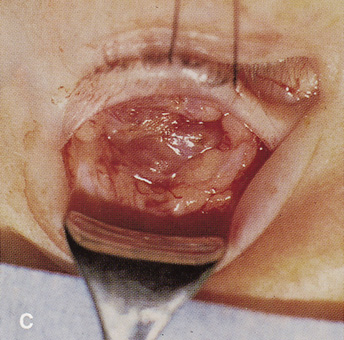

Lesions in the subperiosteal space that involve the orbital floor and roof of the maxillary sinus can be approached through an intraoral incision in the buccal sulcus above the upper canine incisors (Fig. 19). Dissection is carried through mucosa and soft tissue to the periosteum over the face of the maxilla. Dissection is carried superiorly in the subperiosteal plane to just below the inferior orbital rim. Care must be taken to identify the infraorbital nerve as it exits the foramen just below the rim. Osteotomies then are made in the face of the maxilla, and the underlying maxillary sinus is exposed. The sinus mucosa is excised and the roof of the sinus exposed in this fashion. Removal of the sinus roof (the orbital floor) allows exposure of the inferior periorbita. Care must be taken to avoid damage to the infraorbital nerve that runs within the bone of the floor. The inferior rectus muscle is encountered immediately above the periorbita, and it must be protected and retracted during deeper orbital dissection.

Fig. 19. Transantral inferior orbitotomy. The orbital floor (A) (roof of maxillary sinus) is exposed by an incision in the buccal sulcus and removal of the anterior face of the maxillary bone. The infraorbital nerve (B) traverses the floor of the orbit and exits on the face of the maxilla from the infraorbital foramen (C).